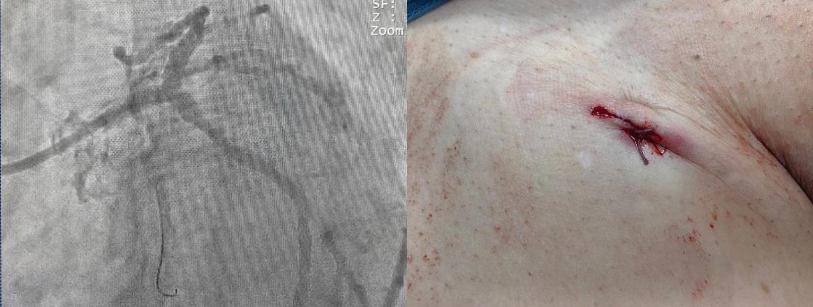

3月7日,西咸院区心内科冠心病介入团队朱舜明副主任医师带领唐治国主治医师、李强强主治医师、张翔住院医师、柳莎莎护士长、崔文宇护师,以及介入导管室团队雷博副护士长、瞿浩主管技师、李炳宇技士,顺利完成物品准备、上机准备、血管评估、穿刺置管等工作,心内科刘博主治医师、梁倩住院医师、刘志远住院医师完成了配血、备血等保障工作,所有医护齐心奋战,整个流程一气呵成,ECMO转机成功。暗红色血液经过膜肺氧合变成鲜红血液,源源不断重返患者体内。术中冠脉造影可见患者左主干末端90%严重狭窄,细小右冠99%狭窄。在ECMO辅助下,心内科介入团队开始进行手术操作。当导丝通过接近闭塞的血管时,患者即出现血流减慢,血压瞬间降至50/30mmHg,透视下心脏几乎不跳动。所有手术人员都捏了一把汗。朱舜明副主任医师迅速指挥抢救,通过提升ECMO转速和流量,并快速用球囊扩张狭窄血管后,患者血流动力学恢复稳定,血压升至110/70mmHg。后续在血管内超声(IVUS)指导下,历时1小时余,完美完成了左主干血运重建。观察患者生命体征平稳后,撤除ECMO并缝合动静脉伤口,体表仅留下不到2cm的痕迹,患者术后胸痛症状明显好转,安返病房,监测生命体征平稳。

介入治疗后造影图及术后ECMO伤口